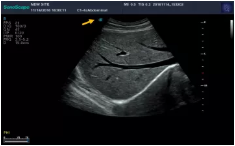

Mark點:每一把探頭都有一個mark點,是用于定位方向, mark點一側始終對應著圖像S點(圖像箭頭標識)一側。

腰椎小關節(jié)